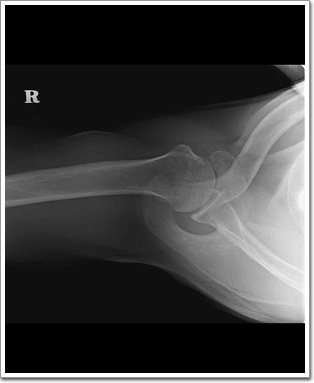

Shoulder Axial

Proximal HumerusFractureDislocation을 진단하는데 매우 유용한 검사 방법이고, 특히 Glenoid of the Scapula Fracture를 진단하는데 중요한 의미를 가진다.

Lesser tubercle의 반측면상이 나타나고, Coracoid processclavicle위에 투영되어야 한다.